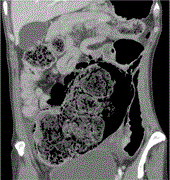

Laparoscopic adrenalectomy for large adrenal tumor guided by a 3D anatomic model. New frontiers in abdominal surgery

Alessio Giordano and others

Journal of Surgical Case Reports, Volume 2023, Issue 3, March 2023, rjad104, https://doi.org/10.1093/jscr/rjad104